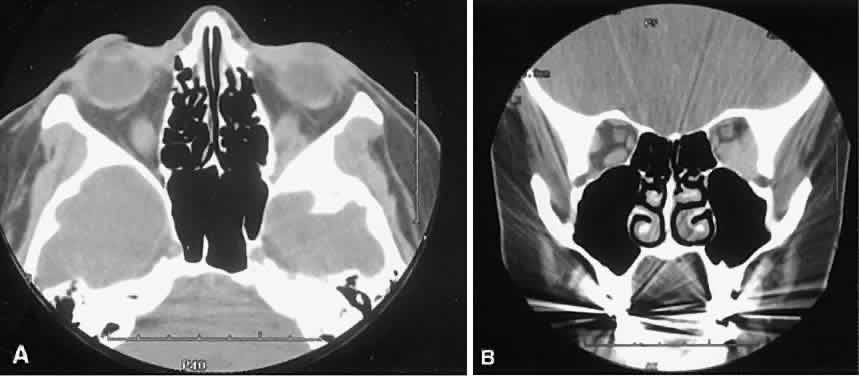

The edema and inflammatory infiltrate that accompany infections are indistinguishable from that associated with orbital inflammations. The presence of sinus disease, however, is a more constant feature with infections, because the sinus represents the infectious nidus in most cases (Fig. 9). In addition to the frequent appearance of sinus disease, the adjacent EOM is invariably enlarged. Less often, orbital infections may be transmitted through the blood, related to a retained foreign body, or spread from the lids. Chandler and colleagues47 classified orbital infections into five groups. Group 1 (preseptal cellulitis) represents inflammatory edema and reflects congestion of venous outflow. Group 2 has actual orbital infiltration/edema with mass effects and functional deficits. Group 3 includes patients with subperiosteal abscesses. Most of these dome-shaped subperiosteal abscesses are located along the medial wall. Group 4 includes patients with orbital abscesses who may display a ring-enhancing lesion with mass effect. Group 5 represents intracranial extension of the inflammation into the cavernous sinus or sinuses, which appear engorged and opacified.

Fig. 9. Orbital cellulitis. A. Axial view shows a subperiosteal soft-tissue mass displacing the medial rectus muscle. The ethmoidal sinus is opacified secondary to inflammatory disease, which invariably precedes the orbital inflammation. B. Coronal view further shows the subperiosteal and ethmoidal sinus inflammation. Inflammation changes also are seen in each maxillary sinus.